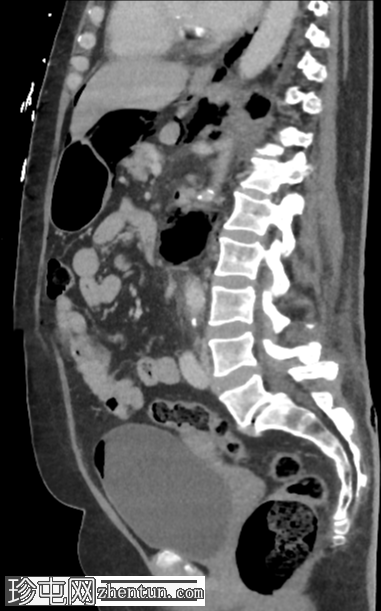

矢状位增强扫描(门静脉期)

左肾广泛破坏,伴有碎裂和气体膨胀

气体延伸至:

左侧输尿管;近端输尿管周围有气体包绕,并可见局灶性输尿管周围碎屑/积聚

进入膀胱

沿左肾静脉进入扁平的下腔静脉(脓毒性休克的特征)

沿十二指肠第二段(D2)进入肝门

进入肾周间隙,伴有坏死碎屑

经肾后间隙进入腰大肌、腹膜前脂肪和体壁

进入肠系膜后间隙、肾后间隙、侧圆锥间隙和联合筋膜间隙,直至股鞘

环绕左侧肾上腺、胃和脾脏,并位于膈下

经食管裂孔和主动脉裂孔进入纵隔

腹腔内气体

不对称性皮下炎症